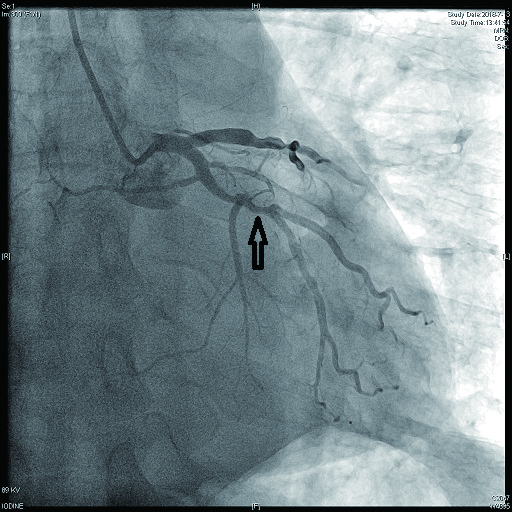

病例4 3 LAD中段及D1(图 11 LAD 85%及D1闭塞 0级 LAD中段植入支架1枚

图 11 病例4冠脉造影示LAD狭窄,D1闭塞